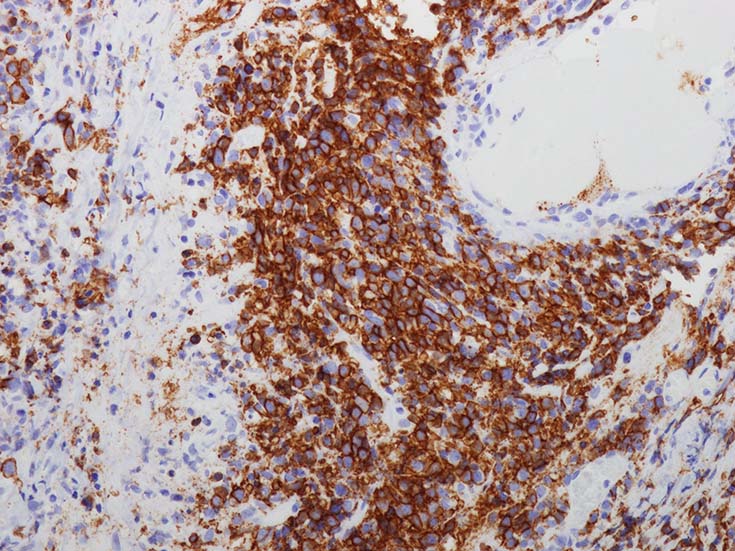

腫瘍細胞はCD20+. CD30の顕著な発現は共通の特徴であるが,CD15の共発現は見られない.

バックグラウンドの浸潤細胞は,小型のT細胞(CD3+,CD4+>CD8+)で構成されている.B細胞はEBER陽性で, EBNA2(+/-); EBV潜伏タイプIIIを示すが, IIの場合も少なくない. (III>II)

EBER-ISH染色は病変のGradeや血管侵襲の程度にもよるが, 陽性B細胞は大小さまざまで不均一である.

血管中心性浸潤. 障害された血管内に血栓が形成されている.CD20陽性細胞がシート状密に浸潤, CD3陽性T細胞が多く混在している. EBER-ISH陽性 EBV感染細胞が多数認められ, >50 hpf, 定義より Grade3となる. 陽性細胞のサイズは大小さまざまであることに注意. Lymphomatoid granulomatosisの病態(WHO5thの診断では EBV-positive diffuse large B-cell lymphomaになる)をとっているが MTX-associated LPDの一型とするべき症例かもしれません.